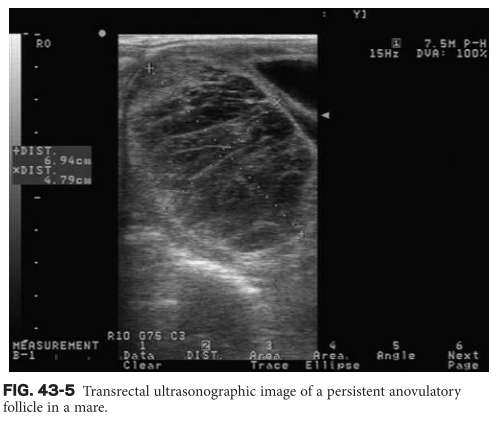

What is the most common cause of ovarian enlargement in mares?

A

(1) tumors

(2) anovulatory follicles

(3) ovarian hematomas

(4) pregnancy

Smith, B. P. (2014). Large animal internal medicine. Ch 43, pg 1319